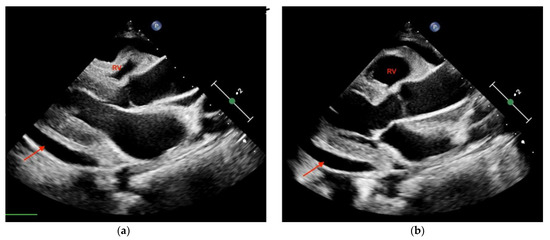

3.4.1. Cardiac Tamponade